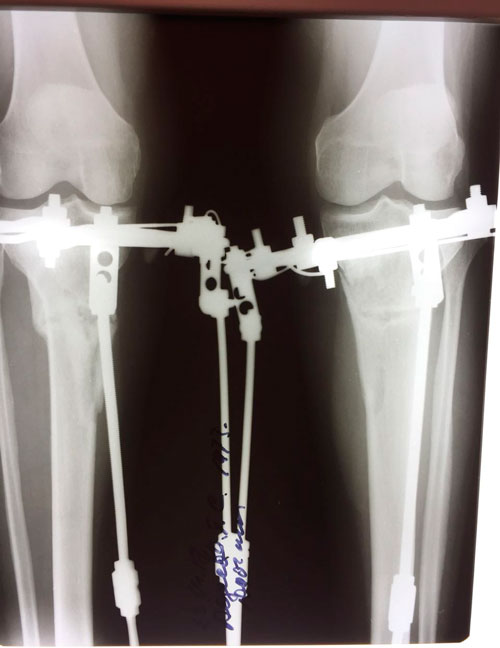

Дата операции 15.01.2018г.

Дата снятия аппаратов 23.04.2018г.

Срок лечения 97 дней.